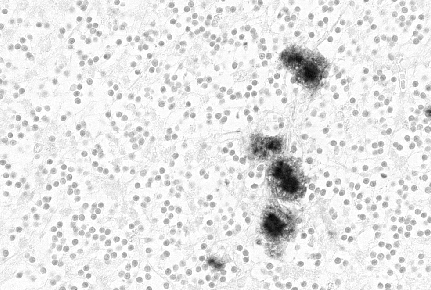

La concentración de la forma patogénica PrPsc en las células se

incrementa progresivamente con la evolución de la enfermedad, llegando a

acumularse en forma de placas amiloides extracelulares.

El desarrollo de la enfermedad viene acompañado por una pérdida

neuronal, cuya patogénesis y bases moleculares aún se desconocen. En

ratones, concentraciones excesivas de PrPc pueden acarrear

neurodegeneración y destrucción de músculos y nervios periféricos. Según

los estudios de G. Forloni [17] la muerte celular se produce por

apoptosis. La secuencia peptídica 106-126 de la proteína PrP posee una

gran habilidad intrínseca para polimerizar in vitro en fibrillas

y/o placas tipo amiloide (las células apoptóticas poseen una morfología

distintiva y muestran un patrón característico de fragmentación del DNA,

resultante de la rotura de DNA nuclear en regiones internucleosomales).